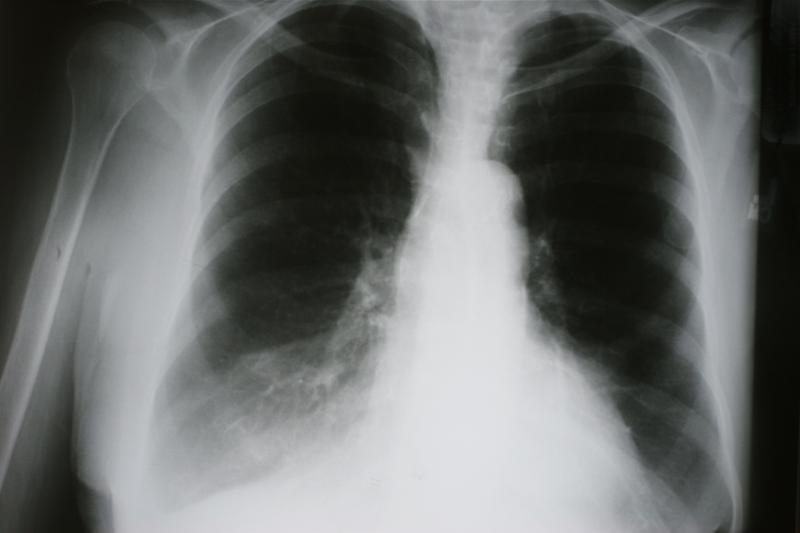

The combination of osimertinib plus selumetinib exhibits antitumour activity in patients with MET-negative, EGFRm advanced nonsmall cell lung cancer (NSCLC), with the safety profile consistent with the reported safety data for the drugs, according to data from the small open-label, phase Ib study.

The study included 47 patients (aged ≥18 years) with MET-negative, EGFR-mutated advanced NSCLC who had progressed on EGFR-tyrosine kinase inhibitors (TKIs). Patients were grouped based on prior first- or second-generation EGFR-TKI (n=12) or T790M-directed EGFR-TKI (n=35). They were given osimertinib 80 mg every day and intermittent selumetinib 75 mg twice a day orally.